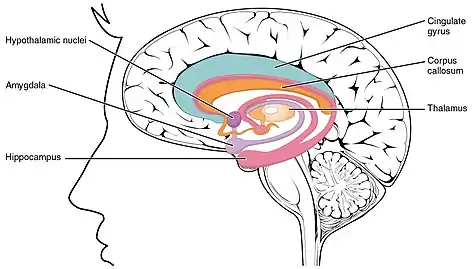

LENAS is seen with damage to the white matter and axons within the brain. The external human LENAS brain shows findings in several major structures. There is mild atrophy of the frontoparietal regions of the brain and a mild reduction of the thalamus and rostral (front) part of the caudate nucleus (which is located in an area of the brain called the basal ganglia).[4] Abnormalities in the frontal, frontoparietal, and temporal lobes are most severe and predominant with LENAS and asymmetry of the cerebral hemispheres has sometimes been found.[4] LENAS also may show moderately enlarged lateral ventricles and atrophy in corticospinal tracts as well as in the pons.[4]

The area where it is seen to be the most pronounced abnormalities appear in the white matter below the pre- and postcentral gyri that extend through the posterior limb of the internal capsule into pyramidal tracts of the brain stem.[4]

- The corpus callosum is variably affected.

- Reactive astrocytes and macrophages are present, but no inflammation appears.

- The cerebral cortex and basal ganglia are normal and contain no or only few spheroids.

- Within the cerebellum, there is a marked loss of Purkinje cells seen but cerebral white matter is normal.